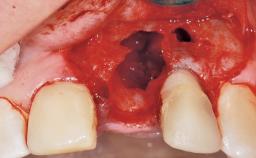

A 29-year-old female patient presented for treatment to replace the upper left central incisor tooth with an implant- supported restoration. The tooth had been intermittently symptomatic for the previous 12 months. The tooth had originally suffered trauma about 15 years previously. Several endodontic treatments had been performed, including an apicectomy procedure to retain the tooth. The patient was healthy and a non-smoker. She had reasonable expectations in regard to esthetic outcomes and the risk of marginal tissue recession following treatment. At medium smile, the gingival margins of the upper teeth were visible, with a display of 3 to 4 mm of the gingival margins. Gingival recession of tooth 21 and a discrepancy in the gingival levels between teeth 11 and 21 was observable during normal speech and smile.

| Socket Integrity | Damage to one or more bone walls |

| Bone Volume | Damage to one or more socket walls |